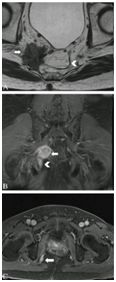

T2加权像粘液性肿瘤呈明显高密度信号,外周蕾丝样增强。MRI检查缺点如下:粘液性肿瘤弥漫性浸润生长已传播至肠壁外,而肠壁解剖结构仍完整;放化疗后即便已无肿瘤、唯留粘液湖时,粘液性肿瘤仍倾向于保持高密度信号(图8);粘液性肿瘤T2加权像呈水样高密度信号,而周围盆腔脂肪也是高密度信号,因此薄层高分辨非压脂轴位T2加权像很易漏诊,此时需调整MRI参数,采用T2加权压脂像抑制脂肪信号,或非压脂轴位T2加权像采用二种不同高回波时间(TE)检测肿瘤,因为周围盆腔脂肪产生二种不同的密度信号(图9)。

图8  65岁女性直肠粘液腺癌放化疗后,轴位T2加权像显示直肠壁粘液池高密度信号(长箭头)和直肠系膜淋巴结(箭头),较前无显著变化,临床定义为无治疗反应,但术后病理证实为粘液池,未见肿瘤细胞。

图9  直肠粘液腺癌。TE 80ms(9A)和120ms(9B)轴位T2加权像显示直肠腔内粘液腺癌不同的高密度信号(星号),右侧肠壁(箭头)和左侧直肠系膜(长箭头),二种TEs信号差别有助于肿瘤检测。9C显示轴位T2加权压脂像,方便检测肿瘤(星号)和肿瘤播散(长箭头)。